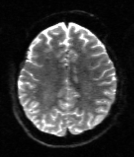

Table 6 reports the runtime and correction quality for PyHySCO using GN-PCG, HySCO, and TOPUP. On real 3T and 7T data, PyHySCO achieves lower loss and higher relative improvement between corrected images than HySCO, and higher relative improvement than TOPUP. The runtime on CPU for real data is 1-2 minutes for HySCO and over 1 hour for TOPUP, while PyHySCO on GPU has runtimes of 10-13 seconds. For the simulated dataset, PyHySCO requires an average of 1 minute on GPU, HySCO an average of 12.6 minutes on CPU, and TOPUP an average of 8.5 hours on CPU. Using the ground truth field maps from the simulated dataset, PyHySCO achieves the lowest average field map relative error, 14.48%, compared to 19.70% for HySCO and 16.36% for TOPUP. Figures 7, 8, and 9 show the field map and corrected images for one example subject from each dataset. The results of the methods are similar, and the resulting field maps are comparable to those of the existing tools, HySCO and TOPUP, while PyHySCO is considerably faster.

Refer to captionRefer to captionRefer to caption+vsubscript𝑣\mathcal{I}_{+v}inputRefer to captionRefer to captionRefer to captionPyHySCO (LBFGS)Refer to captionRefer to captionRefer to captionPyHySCO (GN)Refer to captionRefer to captionRefer to captionPyHySCO (ADMM)Refer to captionRefer to captionRefer to captionvsubscript𝑣\mathcal{I}_{-v}Refer to captionRefer to captionRefer to captionRefer to captionRefer to captionRefer to captionRefer to captionRefer to captionRefer to captionRefer to captionRefer to captionRefer to caption|+vv|subscript𝑣subscript𝑣|\mathcal{I}_{+v}-\mathcal{I}_{-v}|Refer to captionRefer to captionRefer to captionRefer to captionRefer to captionRefer to captionRefer to captionRefer to captionRefer to captionRefer to captionRefer to captionRefer to captionfield map 𝐛𝐛\mathbf{b}Refer to captionRefer to captionRefer to captionRefer to captionRefer to captionRefer to captionRefer to captionRefer to captionRefer to caption+vsubscript𝑣\mathcal{I}_{+v}TOPUPRefer to captionRefer to captionRefer to captionHySCORefer to captionRefer to captionRefer to captionvsubscript𝑣\mathcal{I}_{-v}Refer to captionRefer to captionRefer to captionRefer to captionRefer to captionRefer to caption|+vv|subscript𝑣subscript𝑣|\mathcal{I}_{+v}-\mathcal{I}_{-v}|Refer to captionRefer to captionRefer to captionRefer to captionRefer to captionRefer to captionfield map 𝐛𝐛\mathbf{b}Refer to captionRefer to captionRefer to caption